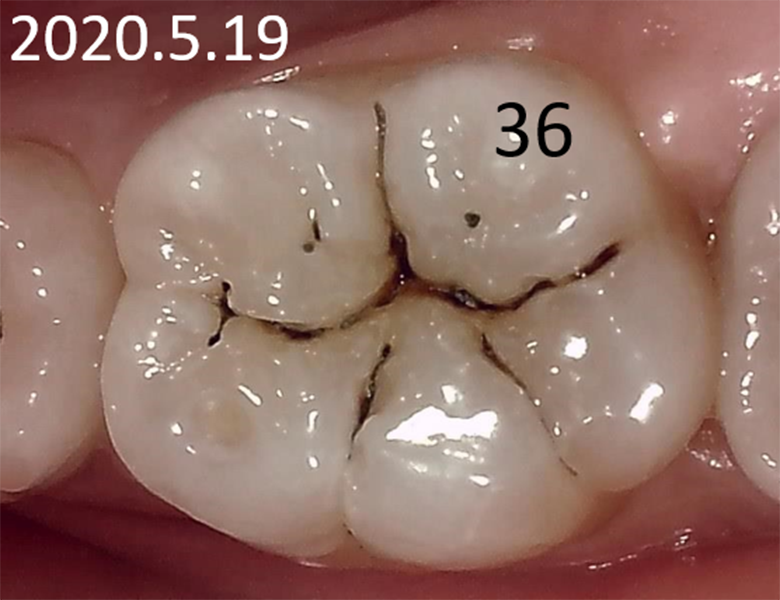

症例② 下顎大臼歯 小窩や裂溝の虫歯 20歳女性

初診時口腔内写真 |

![]() 初診時レントゲン写真 |

このように歯の咬み合う面が虫歯の場合、患者さんが発見することも多く、治療を希望されることがよくあります。

しかし、黒いからと言って安易に歯を削り治療することで、それまでトラブルがなかった歯がトラブルを起こしやすい歯へと変化してしまいます。

たとえ虫歯であっても状態が維持されるのであれば治療の必要はありません。

そして、もし10年後、20年後も変化がなければ治療の必要はなかったと気付かせてくれるでしょう。

歯は一度削ったら二度と元には戻りません。

小さな虫歯であっても安易に治療せず、適切に診査診断を行うことで歯を守ることが出来るのです。